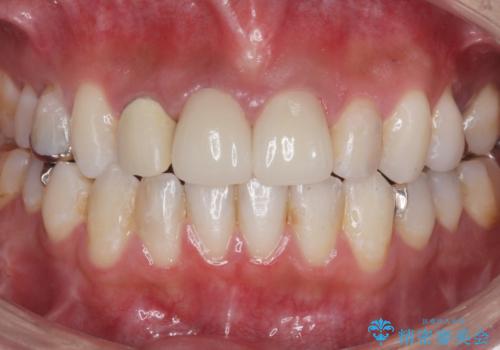

- ジルコニアクラウン・仮歯 12.1万円×2費用は治療当時の料金となります

適合が良い被せ物が入りました。

前歯2本同時に行ったため色もピッタリで患者様に満足して頂けました。